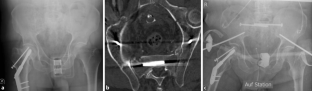

Abb. 1